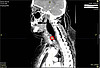

В областную больницу пациентка поступила в тяжёлом состоянии, вызванным сильнейшим обезвоживанием и интоксикацией. В результате компьютерной томографии специалистами было обнаружено инородное тело шейного отдела пищевода (рыбная кость) и флегмона шеи верхнего средостения. Ввиду того, что женщина поздно обратилась к врачам, гнойное воспаление тканей опустилось вниз, в полость между лёгким и сердцем, развился передний медиастинит. Это чрезвычайно опасное для жизни инфекционное воспаление клетчатки средостения, причиной которого стала перфорация пищевода.

КТ пациентки1